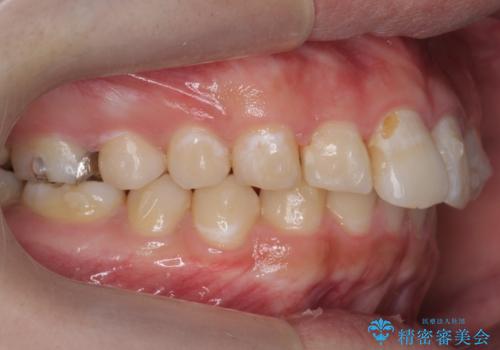

出っ歯が気になる 歯をぬかずに治療

- 前歯が出ているのを気にして来院。

左のかみ合わせが1本分ずれていましたが、機能的には問題ないのでそのまま変えずに治療しています。

ずれている分を、上の歯を1本抜くか(ワイヤー矯正になります)、右上の奥歯を1本分後ろに送るか、そのまま前歯を並べるのかを選んでいただきました。

右のかみ合わせをそのままに、最小限の動かし方で見た目を改善しました。